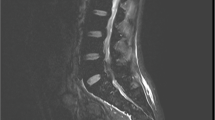

A 62-year-old female with history of rheumatoid arthritis, hip and knee replacements, and chronic low back pain presented with worsening back pain, left leg weakness and pain for 6 weeks, and bowel/bladder incontinence with diminished sensation in the perianal region for 24 h prior to presentation. MRI demonstrated severe spinal stenosis at L4-S1, central disc herniation at L5-S1, and compression of the cauda equina, consistent with CES. A lumbar decompression was performed. Patient did well at 2-week follow up, but presented 5 weeks post-discharge with increased left leg pain/weakness and genitalia anesthesia. Imaging was unremarkable. Two months later, the patient presented with diminished sensation in the buttocks and bilateral lower extremities and bowel/bladder incontinence. Imaging demonstrated a large cystic presacral mass with involvement of the left sciatic foramen and S3 neural foramen. A team of plastic, orthopedic, and neurological surgeons performed an S3 sacral laminectomy, foraminotomy, partial sacrectomy, and S3 rhizotomy, and excision of the large left hemorrhagic pudendal mass. Final pathology demonstrated a perineural cyst with organizing hemorrhage. On follow-up, the patient’s pain and weakness improved.